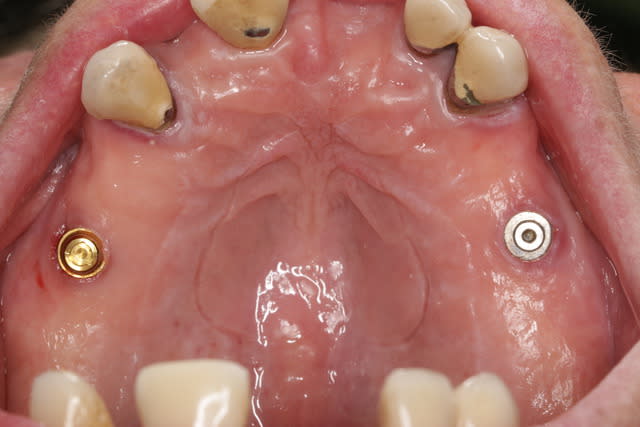

Si une bonne âme, avait la gentillesse d'identifier cet implant d'une patiente ayant fracturé net son Locator, cela me serait bien utile.

Existe t-il un instrument miracle pour dévisser la partie fracturée dans l'implant?

çà, à 99% c'est un biomet 3i...;-)

c'est moi ou on voit un semblant d'hexagone? à moins que tu n'y ais vissé une vis de couv pour protéger?

ça ressemble aussi au Previum S d'easy implant, quoique non je dis une bêtise,sur la radio y a plus d'espace entre les crans à l'apex

Ca ressemblerait à un 3i Certain en 5mm, cependant chez 3i les faces sup. des plateformes implantaires sont anodisées (jaune pour le 5mm), et pas là, mais peut être que la pièce femelle du Locator (toujours en place dans la prothèse amovible de la patiente, et en fonction) a usé cette surface?

Il y a bien un hex. interne au niveau de la vis en place dans l'implant (je n'ai plus qu'à trouver quel tournevis rentre la dedans!)